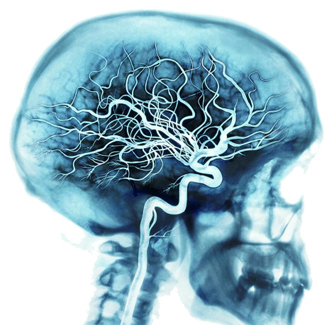

2. 공급선

뇌는 우리몸안에 많은 혈관을 지닌 통로들 중에 하나로 부터 영양분을 공급 받습니다.

심장 박동 때마다 동맥은 우리몸의 약 20-25 퍼센트의 피를 뇌로 보냅니다. 뇌속의 10억개의 세포들은 피속에 있는 약 20 퍼센트에 해당되는 산소와 영양분을 사용합니다.

우리가 생각을 깊이하게 되면 우리의 뇌는 50퍼센트 까지 그 산소와 영양분을 사용하게 됩니다. 뇌속에 있는 혈관 조직은 동맥 정맥, 모세혈관 모두를 포함합니다.